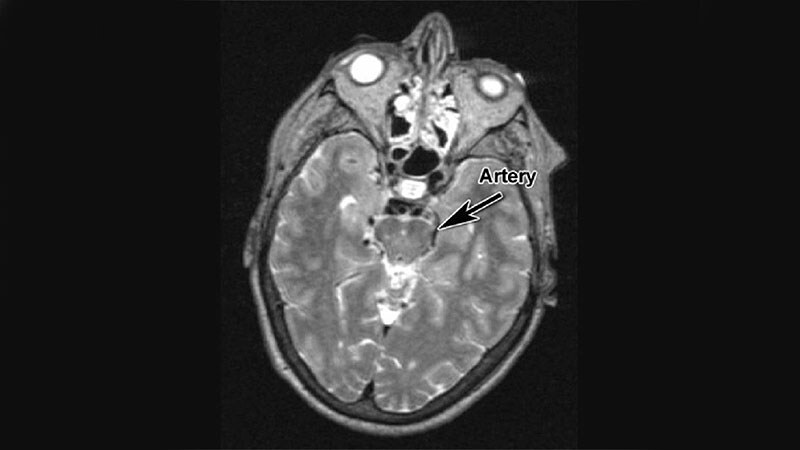

More Evidence COVID 'Brain Fog' Is Biologically BasedPatients with 'brain fog' during acute COVID-19 had the highest levels of inflammatory markers, offering additional evidence

of a neurological basis for post-acute sequelae of SARS-CoV-2 infection.